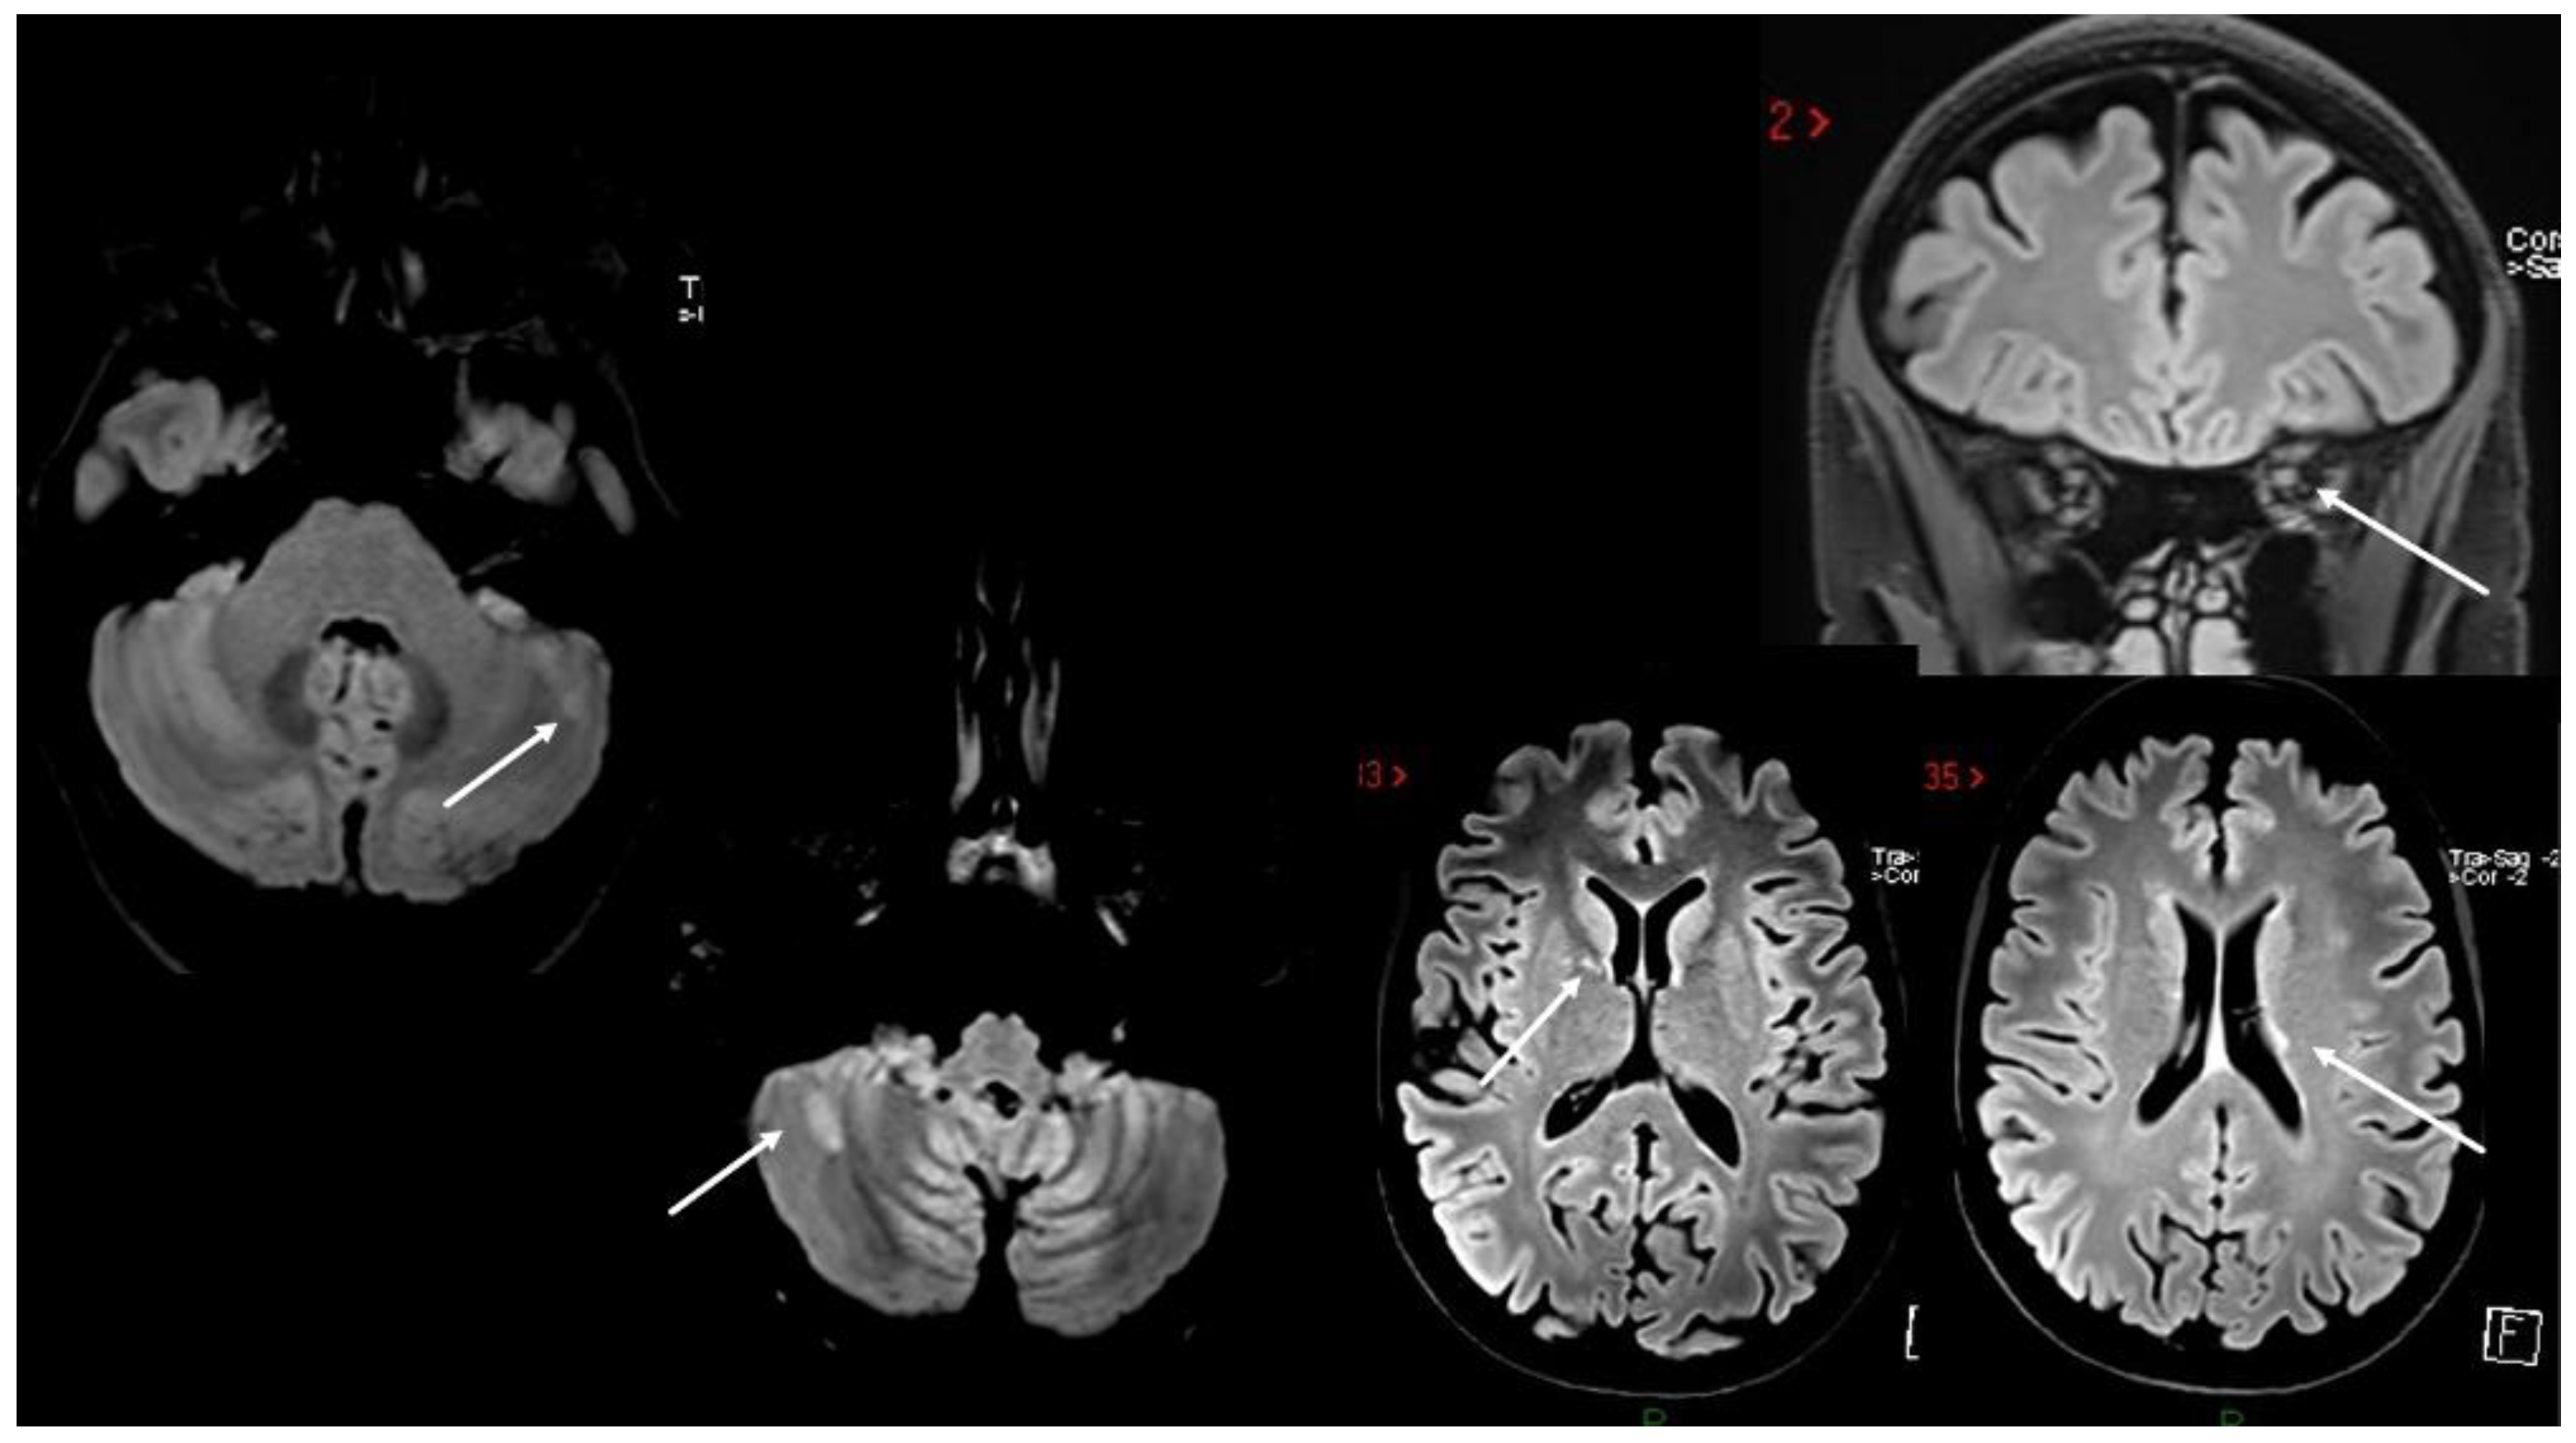

4. MS Onset after Vaccine Exposure

| Case 6 | BNT/2nd | 2 weeks | Multisymptomatic (gait/trunk ataxia, sphincter) | (MRI not in acute phase) | + | + | -/- | |

| Case 7 | ChAdOx1/1st | 1 week | SC | + | - | + | -/- | |

| Case 11 | BNT/1st | 1 week | SC | SC | + | + | NA | |

| Case 12 | BNT/1st | 2 weeks | SC | SC | + | + | +/+ | |

| Lee et al. [51] * | Various | 0–55 days | Mainly SC | Various sites | variable | various | +/+ | |

| Czarnowksa et al. [62] | JJ/1st | 2 weeks | SC | Brain, SC | + | + | +/+ | |

| Havla et al. [95] | BNT/1st | 1 week | SC | SC | + | + | +/+ | |

| Khayat-Khoei et al. [64] 3 cases | mRNA vaccines/ 2nd (2) | 2–3 weeks | ON (2) SC (1) | Brain (1) SC (2) | + | NA | -/+ | |

| Kaulen et al. [65] | BNT (4) | 2 weeks | ON (4) SC (2) ST (2) | ON (4) SC (2) ST (2) | + | +/+ | ||

| Mele et al. [66] | Mod/1st | 2 days | Cerebellum | ST | + | + | −/+ | |

| Rinaldi et al. [68] 2 cases | BNT/1st (1) 2nd (1) | 1 week | BS+SC (1) ST (1) | BS+SC (1) ST+ SC non-ce (1) | + | + | +/+ | |

| Gernert et al. [63] 5 cases | BNT (4, 3 cases 1st, 1 case 2nd), 1 ChadoOx/2nd | 1–2 weeks | ON (2) BS (1) SC (1) BS+SC (1) | SC (2) BS/cerebellum (3) | + | +/+ | ||

| $ Watad et al. [69] 4 cases | BNT/1st (2) Mod/2nd (2) | 1 day–1 month | ST (1); cerebellum, SC (1) SC (2) | + | + | + | +/+ | |

| $ Nistri et al. [67] 2 cases | ChadOx/1st | 1 week | ON (2) IT (1) | + supratentorial | + | + | -/- | |

| Toljan et al. [70] 4 cases | BNT/1st (2) | Uncertain | + | + | + | -/- | ||